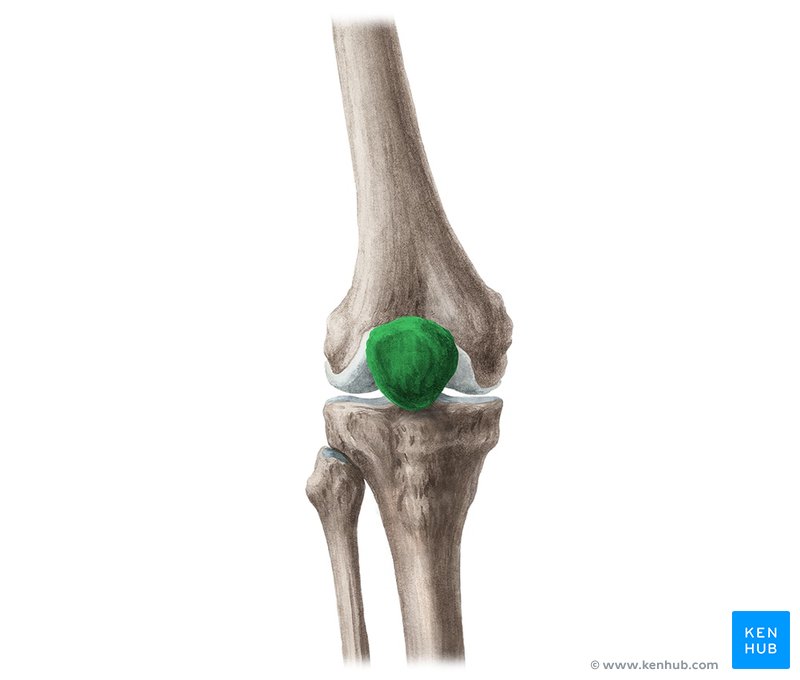

What is this region?

Patella